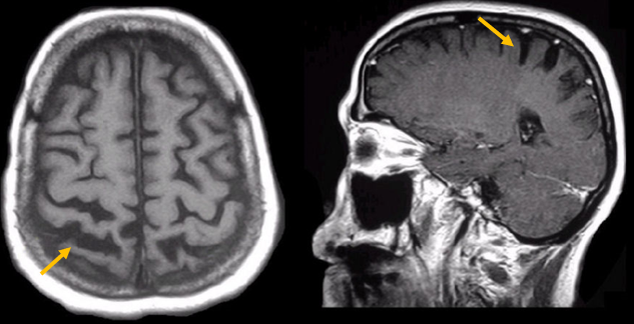

피질 기저핵 변성은 비대칭 증상을 두드러지게 보인다는 점에서 파킨슨병과 비슷합니다. 그러나 파킨슨병과 비교해 보았을 때 양측의 차이가 아주 심하게 나타난다는 특징이 있습니다. 질병 초기에 한쪽 손으로 동작을 하거나 계획된 행동을 하는 기능이 현저하게 떨어집니다. 간단한 손가락 모양도 따라 하지 못하는 현상을 보입니다. 또한 의지와 상관없이 제멋대로 움직이는 통제불능 손이 나타날 수 있습니다. 체위 떨림, 경축, 운동 완만과 같은 파킨슨병에서 볼 수 있는 증상들은 피질 기저핵 변성에서도 관찰될 수 있습니다. 또한 집중력 장애, 수행 장애, 이름 대기나 언어의 유창성이 떨어지는 등 전두엽 및 두정엽과 관련된 인지 장애가 나타납니다. 피질 기저핵 변성은 뇌 자기공명영상(MRI)에서 증상의 반대쪽 전두두정엽의 위축 소견이 특징적으로 나타납니다. 뇌포도당 양전자 단층촬영(PET)에서도 전두엽, 뇌기저핵에 비대칭적인 대사 저하의 소견이 보입니다.

[피질기저핵 변성 환자의 뇌자기공명영상에서 확인되는 비대칭 뇌피질의 소견]

[피질기저핵 변성 환자의 뇌포도당 양전자 단층촬영에서 확인되는 비대칭적인 대사 기능 저하]